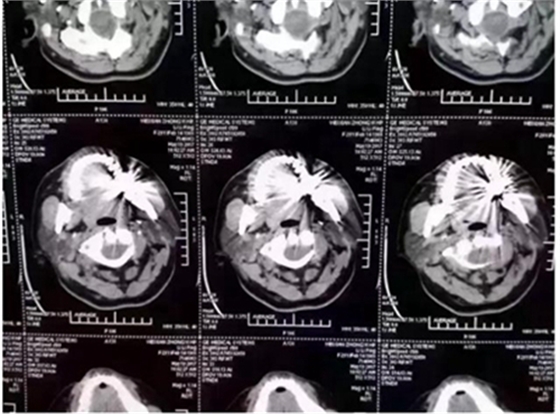

這幾天,一張照片刷爆了牙醫(yī)朋友圈

對這張照片,有牙醫(yī)評論如下:

口內(nèi)有金屬烤瓷牙做核磁共振,CT,以烤瓷牙為中心呈現(xiàn)放射狀影像,無法看清周圍組織,影響臨床診斷,建議條件允許的朋友還是選擇二氧化鋯全瓷冠修復(fù),以免帶來不必要的麻煩!